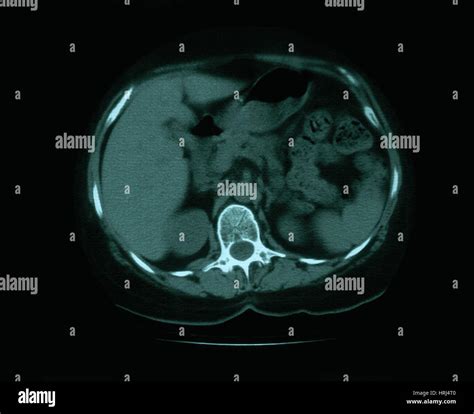

• CT Scan: A computed tomography (CT) scan provides detailed images of the lungs and can help identify the location and extent of the calcification.